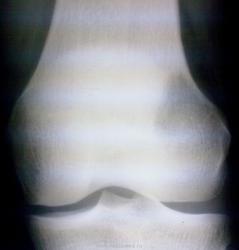

Женщина 24 лет, локальная болезненность по наружной поверхности левого коленногосустава. Боль началась около 2 мес. назад, постепенно усиливаясь но не до критического. Отека, покраснения нет, хотя отмечает локальную гипертермию, усиление боли при пальпации. К какому типу патологии можно отнести данную Ro картину?

Тип деструкции - литический. Наиболее вероятна опухоль. Я предполагаю, как наиболее вероятную с учетом возраста, клиники, локализации и рентгеновской картины, гигантоклеточную опухоль. Но возможны варианты. К онкологу, на биопсию.

А когда я оформлял это клиническое наблюдение - нужно было отметить ряд вопросов, в т.ч. тип патологии. Вот я и притормозился (локальная деструкция, без четкого отграничения, кортикальный слой не нарушен, окружающая костная ткань б/о, мягкотканного компонента не видно. Вначале сделали колено в 2-х пр. - думали наваждение какое, если бы не клиника. Потом сравнительная Ro-гр с здоровым коленом), отметил "другое".